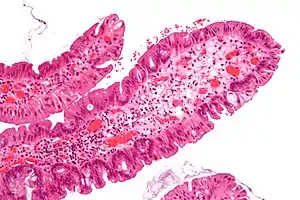

| Hyperplastic polyp of the stomach | Stomach | Elongated, tortuous, and cystic foveolae separated by edematous and inflamed stroma.[4] | ![]() |

Gastric hyperplastic polyposis | |